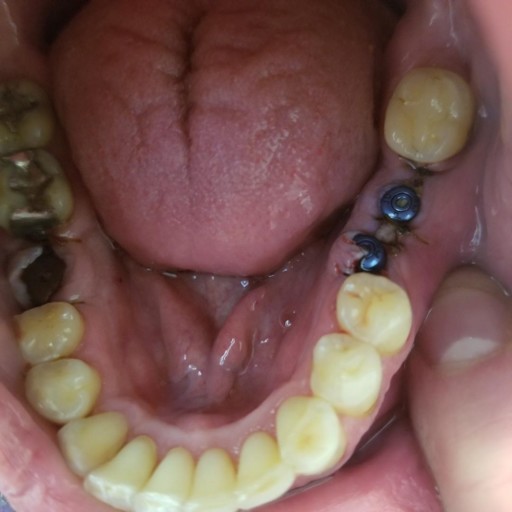

Hi, My Name is Steven Kinlin I\'m almost 44 years of age. I\'m not 44 years Old mentally as I have Aspergers Syndrome and other disabilities. I have a big everbite. I have 4 teeth that are not completly gone but there broke. See I was seeing a Dentist in my Town Of sharon Massachusetts. And he would tell me that my fillings were old and needed to be replaced. And I was a little Nieve So I had the fillings replaced. And I think what I sahould have done was waited until the fillings actually came out. I should have realized that just because they were old doesn\'t necessaraly mean that they will fall out and need to be replaced. so he did that and Most of the original tooth was gone most of it was Filling. So I would eat different foods and Sandwiches and a piece of the tooh would come off. Now these are all top teeth the bottom teeth I\'m not missing any.I have a couple of crooked teeth at the bottom but none that are missing. And one on the top right in front kind of a big square tooth I guess that most of it is filling. I also have one tooth on top that\'s gone that\'s just got the post I guess the root is still there but the nerve has not been removed. The reason for this is because several years ago back in maybe 97 This tooth was really bothering me with pain. And the dentist I was talking about Dr allen Gouchman said that I needed a root canal.

So he did the root canal and made another tooth. I guess though that I did not have enough anchorage. Or jaw bone to support the new tooth because after about 8 years The tooth came out leaving me with just a metal post if you will call it that. And he said that he couldn\'t do another root canal since that gap got smaller that My only option was a dental implant. So I never got it I just left it there because I don\'t have enough of a strong anchor I guess for Dental Implants. That\'s not what he said. When One of the 4 teeth broke I went to Aspen Dental. and they said that they wanted me to have a teeth scaling or a gum scaling. Which I did not do because part it is fear and the other part is that mass health wouldn\'t pay for it and I could not afford it or find other places that would take mass Health either. So they said that even having the teeth scaling that I wouldn\'t be able to get dental implants until I got invisalign. and maybe had more Bone put in my jaw so that I would have a strong anchor for dental implants so that the dental implants, I guess, would not fall out. The reason I didnt get Braces when I was a kid is because my parents didn\'t think that I wouls stick with putting in new elastics everyday.

And they were right. So I never got Braces. So It seems Like invisilign is the way to go. and then after that I have heard that I will be able to get dental implants. The only requierment is that you have sufficent Jaw bone but they can also add jaw bone to give me enogh for dental implants. Also have you heard of an aclusal Adjustment I spoke with a dentist a while back online who said to get an aclusal adjustment because that may make the appearence of the overbite look better. I\'m not sure if I would need the aclusal Adjustment if I got Invisalign. It would Only be for a couple of teeth. I think, the ones that just about come in contact with my bottom lip. Are any of the procedures that I mentioned here painful? I hope not.I still would want these teeth shaved down a little bit. I have kind oif a small mouth ,but that I don\'t think would matter. Well thank you so much!If there is any other info I can think of I will let you know Sincerely Steven Kinlin